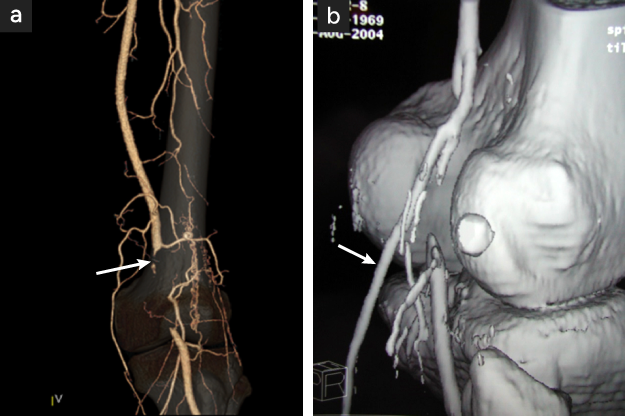

図2

図2. 左膝窩動脈外膜嚢腫の血管造影

膝窩動脈狭窄像(矢印)